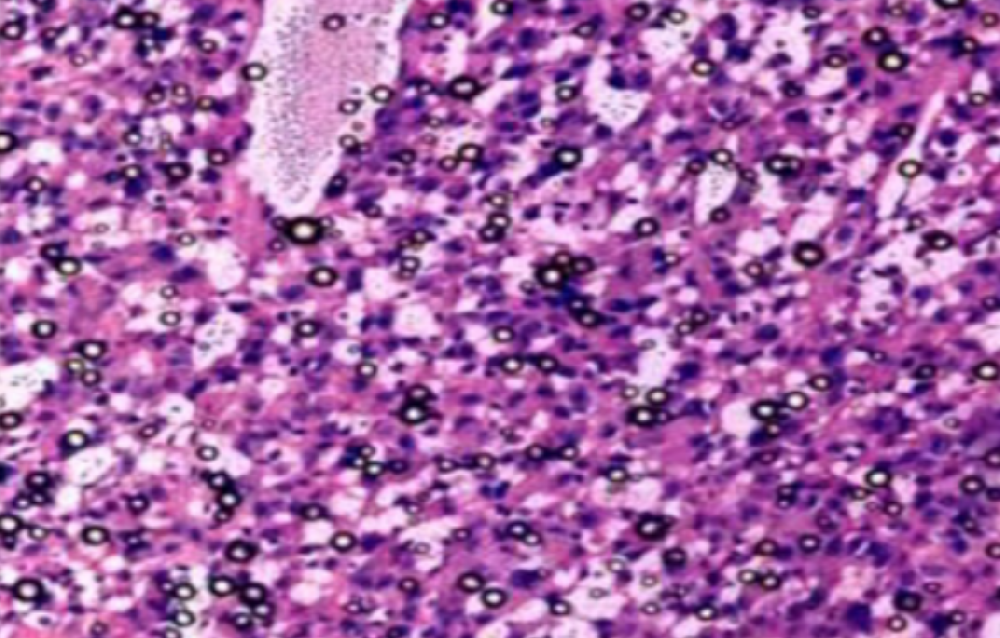

HE染色,全称苏木精-伊红染色法(Hematoxylin and Eosin staining),是最常见的组织切片染色技术之一,用于在显微镜下观察和分析组织或细胞的结构和形态。虽然HE染色是最常见且最基础的染色技术之一,😭但在实验过···

HE染色,全称苏木精-伊红染色法(Hematoxylin and Eosin staining),是最常见的组织切片染色技术之一,用于在显微镜下观察和分析组织或细胞的结构和形态。

虽然HE染色是最常见且最基础的染色技术之一,😭但在实验过程中,很容易出现各种情况导致染色切片质量参差不齐。所以,小编根据以往实验经验,给大家整理归纳出了15个HE染色中的常见问题,还包含问题原因分析以及解决方法哦~